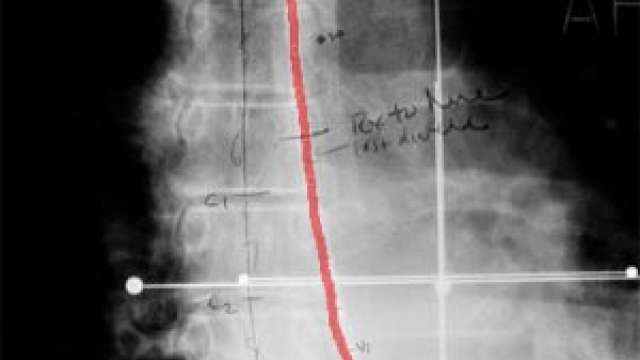

Esophageal And Bile Duct Cancers

The treatment of esophagus and gall bladder cancers is similar in that they are both treated using "intralumenal" catheters. (A lumen is the hollow space in the center of a tube).